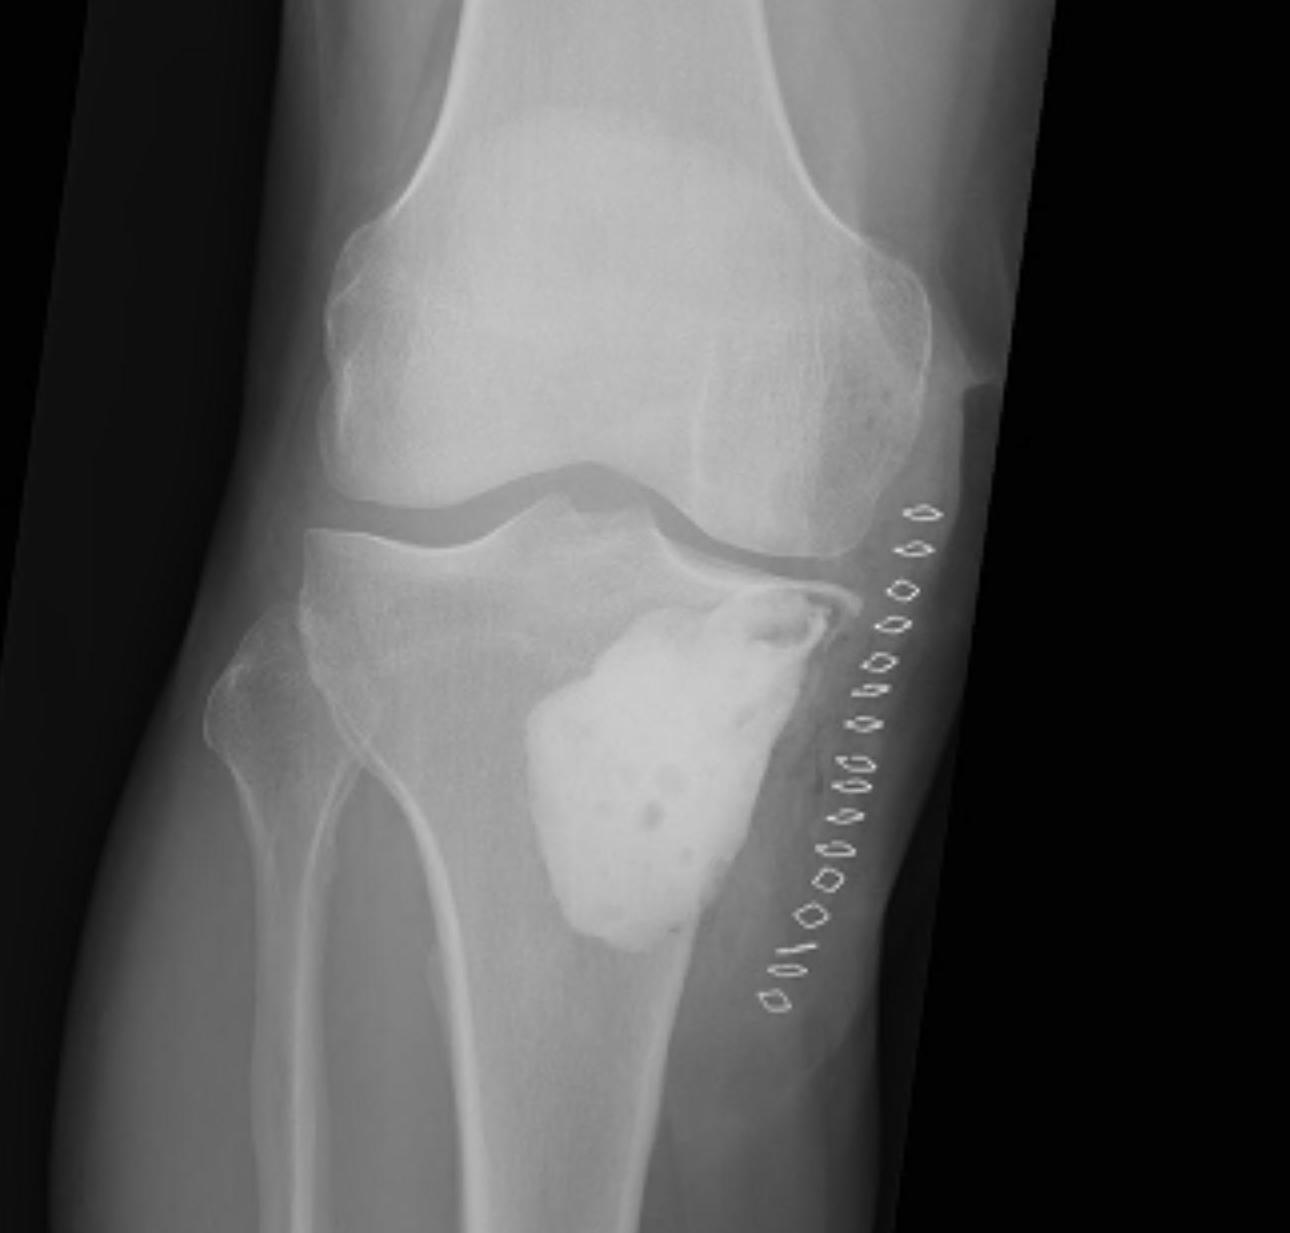

X-ray

Well defined eccentrically located epiphyseal lesion

- thin sclerotic reactive rim

- may have calcification

Evaluate articular surface integrity / compromise

Identify chondroid matrix